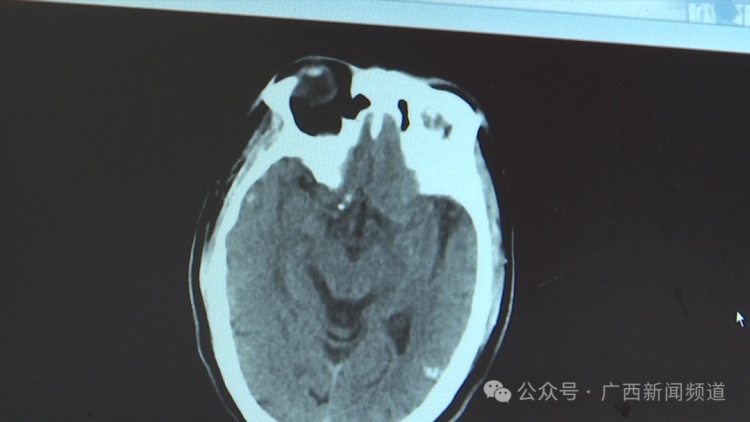

广西民族医院神经内科三区主任 胡瑞婷 他的诊断的话是这个脑囊虫病引起的继发性癫痫,大概是从2020年发病的,主要是因为他一些比较特殊的饮食习惯造成的,比如说喜欢吃一些生的猪肉、猪血或者是这一类的。

现场讲解 这个CT的话我们就可以看到他脑部的像大脑镰,左边的顶叶都是有高密度影的,这就是我们说的寄生虫的结节,右边的额叶这个位置也是有高密度影,旁边还有一些水肿带,那就说明它的炎症反应还持续存在。